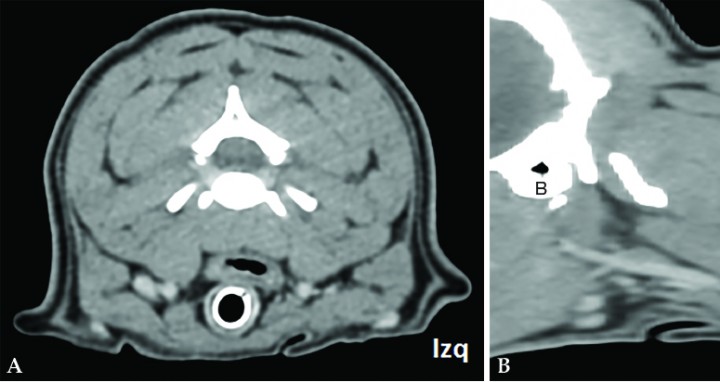

En la TC se identifica la presencia de una masa cervical izquierda (3 cm de alto x 4 cm de ancho x 5,3 cm de largo), originada en el área de la carótida común izquierda y vena yugular interna a la altura de C3-C4 (Figs. 1 y 2A). Las tiroides resultan dentro de la normalidad. En el estudio poscontraste la masa realza de manera marcada y heterogénea. En su extensión dorsolateral, la masa se extiende hacia la porción dorsal, sobre todo izquierda, de laringofaringe y esófago craneal, causando efecto masa desplazando a la derecha la laringe y aparato hioideo, y ventrolateralmente a la derecha el esófago craneal (Figs. 2B y C). También desplaza dorsolateralmente a la izquierda la musculatura cervical hipoaxial, y la porción más rostral en el lado izquierdo se extiende dorsalmente hacia la base del cráneo, pero no se detecta infiltración intracraneal ni signos de lisis ósea en la base del cráneo (Fig. 3). Aunque la masa parezca bastante bien definida no se puede descartar una afectación de la laringe/laringofaringe y de la musculatura cervical. Se visualiza también una congestión venosa y arterial regional (arteria carótida común y vena yugular interna izquierdas) secundarias a la masa, y aunque no se detectan signos de trombosis u oclusión, no se puede descartar una invasión vascular de estos vasos que están envueltos por la masa.

<p>Imágenes de TC poscontraste en ventana de tejido blando de la masa cervical izquierda. (<strong>A</strong>) Plano sagital. (<strong>B</strong>) Plano dorsal. (<strong>C</strong>) Plano transversal. Nótese el desplazamiento de la laringe (*). M: masa; A: atlas; B: bulla timpánica izquierda.</p>

Figura 2

Imágenes de TC poscontraste en ventana de tejido blando de la masa cervical izquierda. (A) Plano sagital. (B) Plano dorsal. (C) Plano transversal. Nótese el desplazamiento de la laringe (*). M: masa; A: atlas; B: bulla timpánica izquierda.